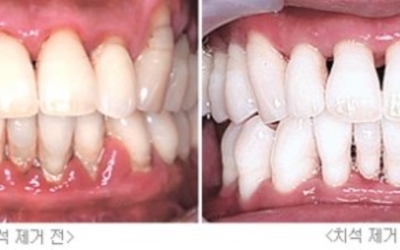

1. 스케일링

잇몸 질환은 플러그가 누적되어 염증으로 발전해 발생되는 것이므로 치석을 제거해주는 스케일링을 정기적으로 받는다면 좋은 잇몸을 유지할 수 있답니다. 스케일링의 경우엔 보험이 적용되기 때문에 1-2만 원 정도의 저렴한 비용으로 받을 수 있기 때문에 필수로 정기적으로 받아보시기 바랍니다.